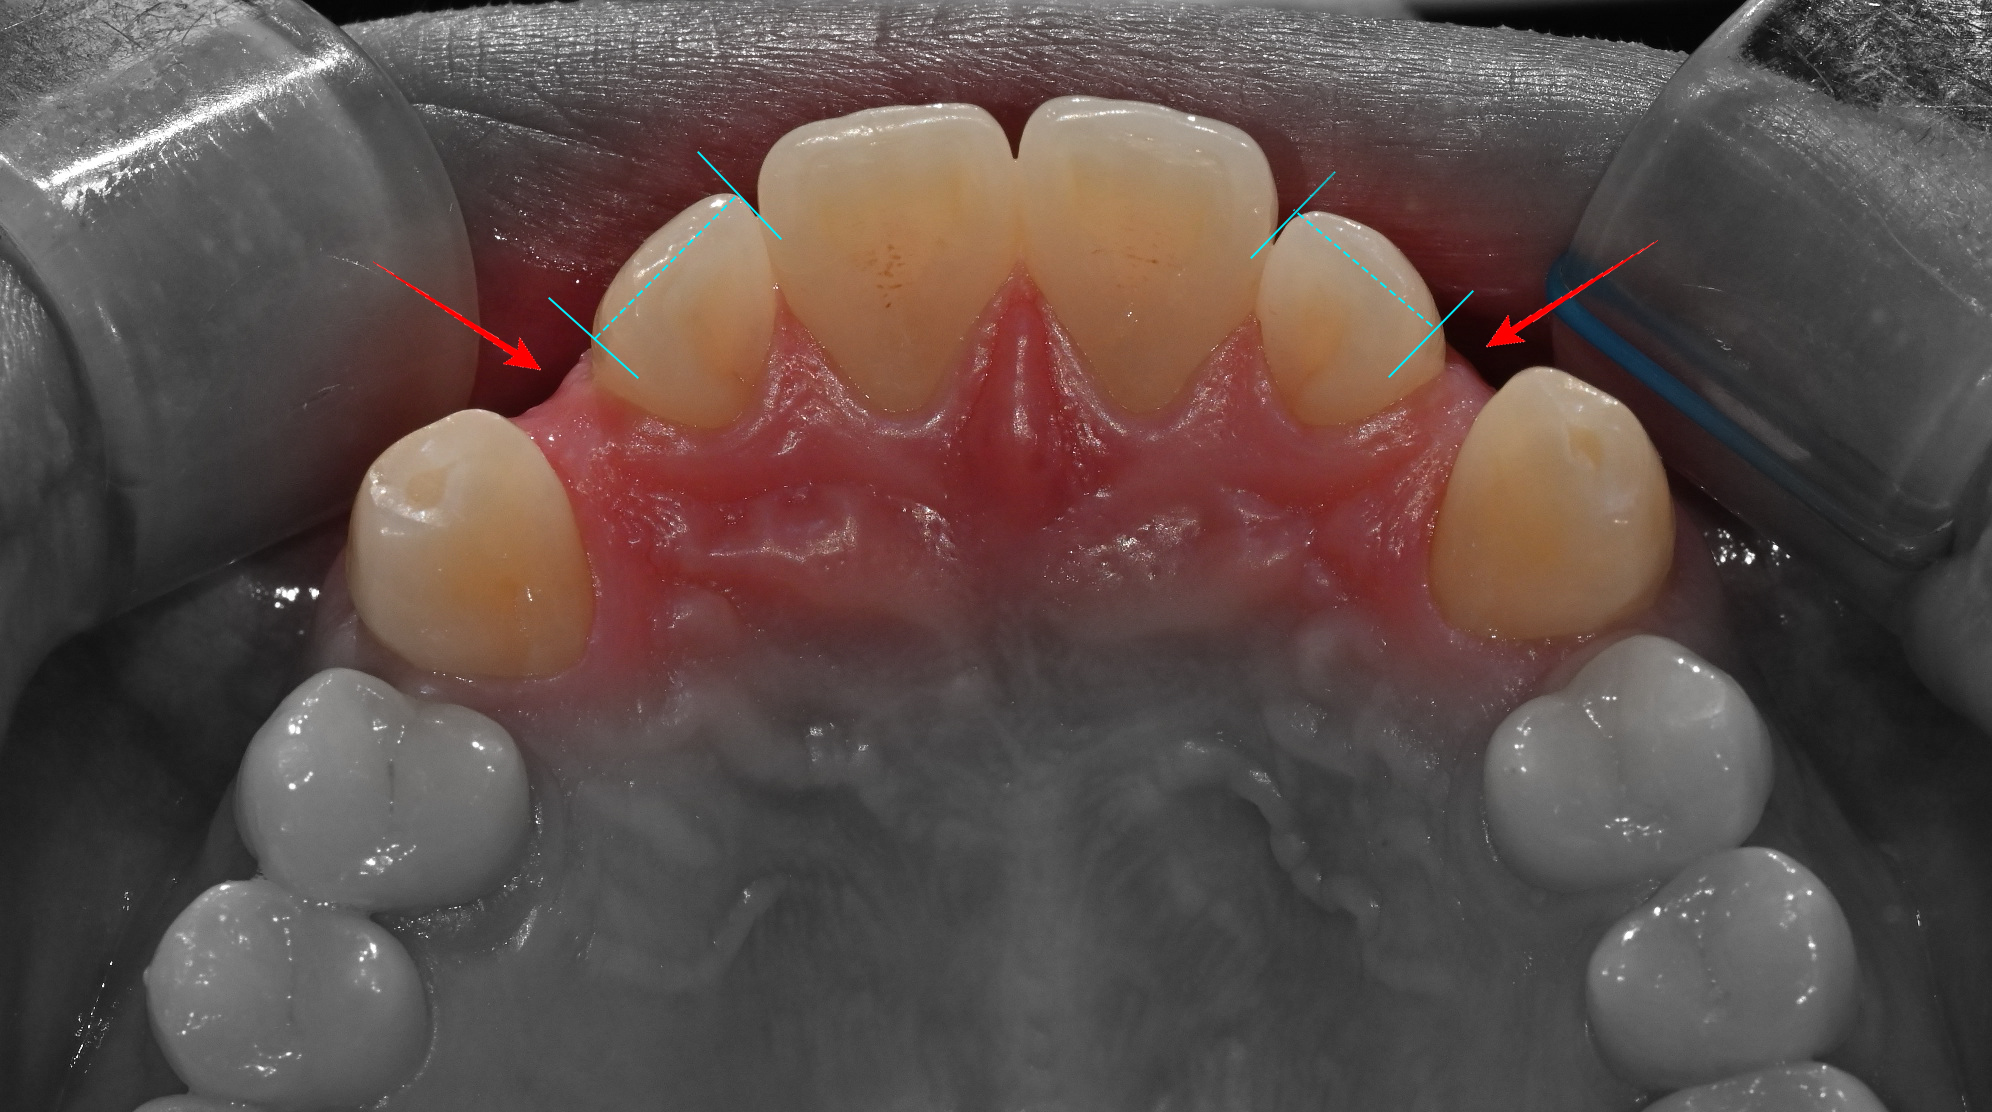

교정 후 크라운 치료, 디테일이 결과를 좌우한다

인비절라인 교정을 통해 이상적인 치아 배열과 공간 확보가 완료되면, 인접 치아의 형태, 색상, 표면 질감 등을 세밀하게 분석하여 다음과 같은 완성도 높은 크라운을 제작할 수 있게됩니다. ^^

치료기간 : 23.12.19 ~ 25.07.17